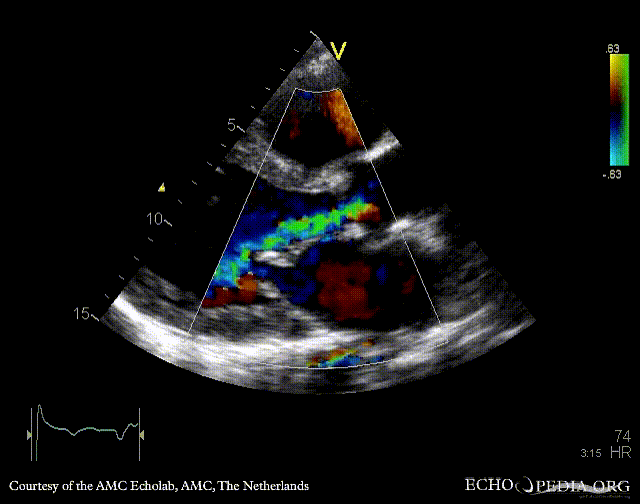

PSAX: thickend aortic valve PLAX: severe aortic and mitral regurgitation